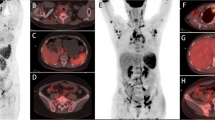

In the four patients that performed 99mTc-WBC (Fig. 3), early images (when no bowel activity is detectable in normal subjects) showed the variable presence of radiolabelled leukocytes in the right colon, a sign of their migration in the bowel wall. One patient also clearly showed activity in the caecum and left colon. No detectable activity was found in the lungs. Remarkably, when patients recovered from COVID-19, they did not have any activity in the bowel, and the bone marrow also showed less uptake as compared to the scan at diagnosis.

Anterior view of the abdomen was acquired 2 h after intravenous injection of radiolabelled leukocytes in 4 patients at the time of diagnosis of COVID-19 (B, E, I, L) and at recovery (C, F, J). All patients show the presence of radiolabelled autologous leukocytes in the right colon (solid arrows) and in the caecum (dashed arrow) and left colon (dotted arrow) in one case (L). Scans performed after recovery from COVID-19 (C, F, J) do not show any activity in the bowel. Bone marrow activity is also lower at recovery as compared to diagnosis. Maximum intensity projection (MIP) images after [18F]FDG of the same patients are also shown at the time of diagnosis (A, D, H, K) and after recovery (G). Activity in the lungs is clearly visible, as well as activity in the bowel (solid black arrows)